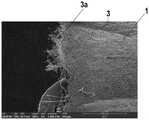

图2示出了通过根据本发明的方法生产的管腔内的内假体的扫描电子显微镜记录的图像,该内假体具有由金属合金制成的支撑结构(支架)和可生物降解的电纺聚合物护套;Figure 2 shows an image recorded by scanning electron microscopy of an intraluminal endoprosthesis produced by the method according to the invention, the endoprosthesis having a support structure (stent) made of a metal alloy and biodegradable electrical Spun polymer jacket;

图2示出了通过根据本发明的方法生产的管腔内的内假体1的扫描电子显微镜记录的图像,该内假体具有由Co-Cr合金(L605)制成的支撑结构(支架)2和可生物降解的电纺聚合物护套3。Figure 2 shows an image recorded by scanning electron microscopy of an